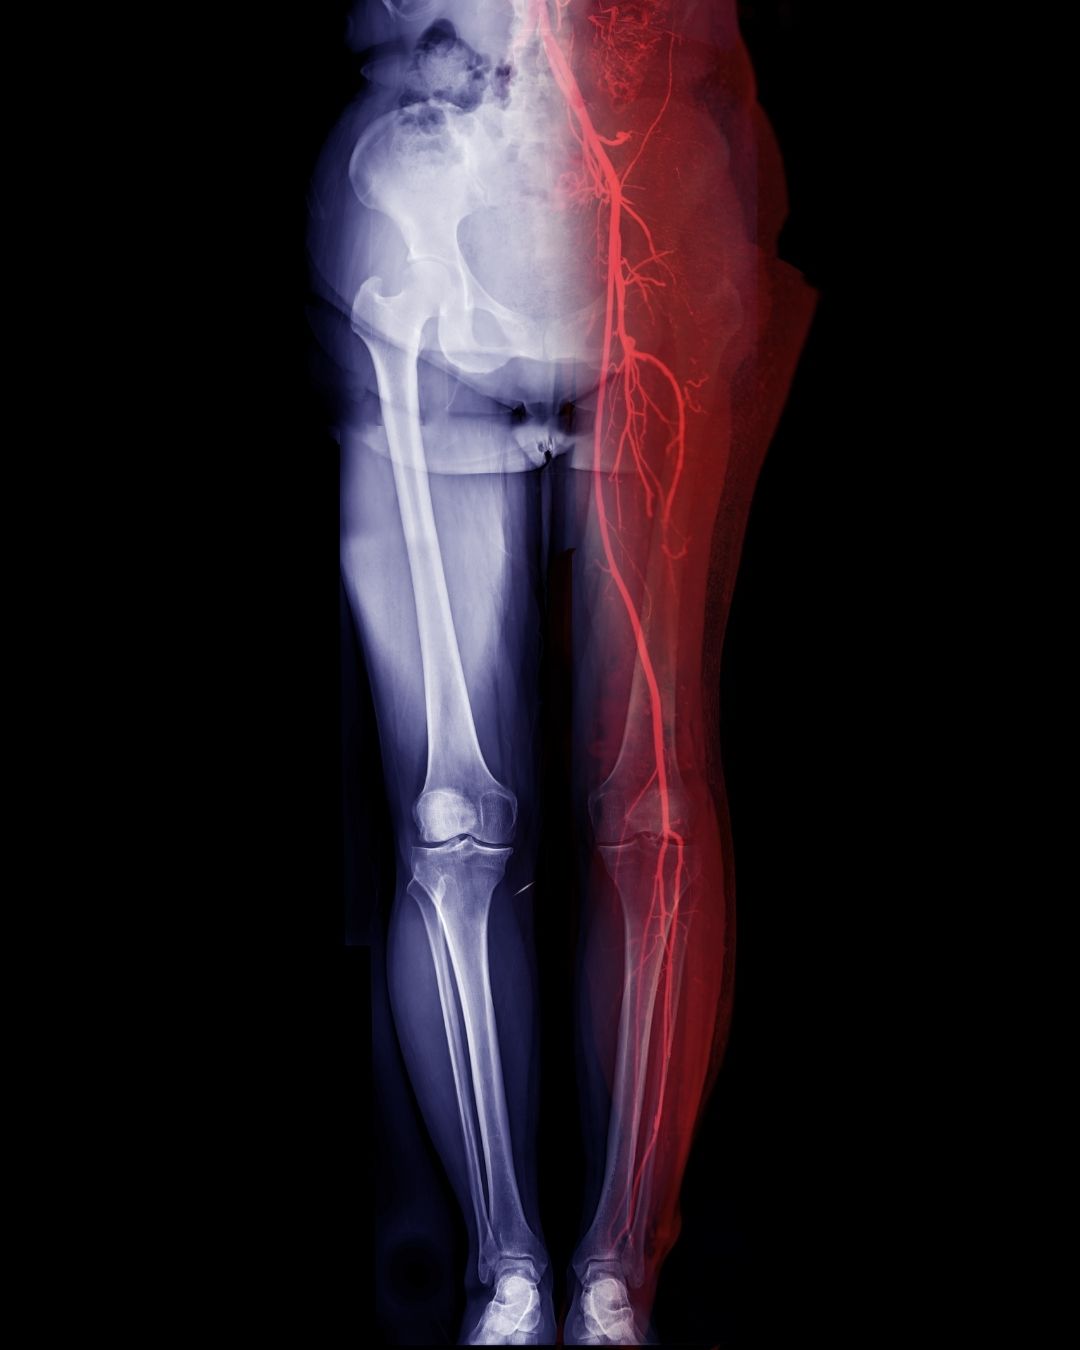

Bilateral Alt Ekstremite BT Anjiyo, her iki bacak damarlarının Bilgisayarlı Tomografi (BT) ile anjiyografik olarak görüntülenmesi işlemidir.

• Bacaklardaki atardamarların (özellikle iliak, femoral, popliteal, tibial arterler) durumu incelenir.

• Damar tıkanıklıkları, daralmalar, pıhtı (tromboz), damar sertliği (ateroskleroz), damar yapısal bozuklukları (anevrizma vb.) saptanır.

• Bu madde damarların içini boyar ve BT cihazı damarların üç boyutlu görüntüsünü çıkarır.

• İnceleme genellikle kasıktan ayağa kadar tüm damar sistemini kapsar.

Kısacası, Bilateral Alt Ekstremite BT Anjiyo, iki bacağın damar yapısını ayrıntılı olarak inceleyen ileri bir görüntüleme yöntemidir.